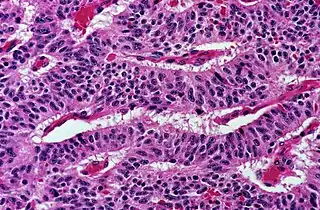

Architectural pattern of any suspicious cells, in this case nests of cells, as well as components of the intervening stroma.

Cellular arrangement, including crowding and cell polarity (common tendencies among cells at the border, such as elongation or "palisading" in this case). Amount of mitoses can also be appreciated at this level.